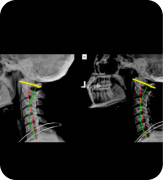

“After years of constant neck pain from poor posture, X-rays revealed alignment issues caused by desk work. Through chiropractic care and corrective exercises, my neck curve improved, and my pain completely disappeared within weeks.”